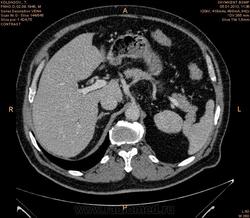

Помогите разобраться.Больной 2 мес назад обследован на узи бр.полости  чисто.(м.б. не опытный узист.)Беспокоять боль в правом подреберье, потеря веса нет.Анализы еще не готовы.

Гиподенсное образование в 8 сегменте, с накоплением по контуру в артериальную фазу, заполнением почти полностью в портальную, и опять гипо- в отсроченную. Пока думается на гемангиому, дифференцировать с гепатоцелюллярным раком, несмотря на отсутствие признаков цирроза. Сложновато  без дайкома.

Судя по времени, отсроченная через 7-8 мин от начала введения контраста (ФИО пациента убирайте, пожалуйста!). На мета, на мой взгляд, не похоже. Подождём, что еще коллеги скажут.

Вымывание контраста к венозной и равновесной фазам если не путаю более характрено для HCC.

имеет значение количество и скорость введения контраста

без диком создается впечатление что контраста либо мало было либо низкая скорость